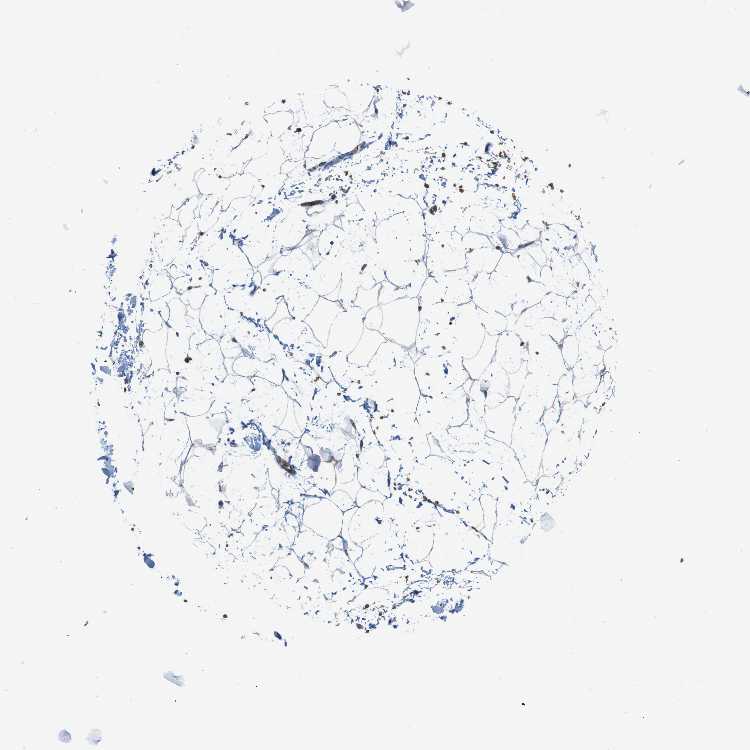

SOFT TISSUE 2 - Antibody stainingi

Antibody staining in the annotated cell types in the current human tissue is reported as not detected, low, medium, or high, based on conventional immunohistochemistry profiling in selected tissues. This score is based on the combination of the staining intensity and fraction of stained cells.

Each image is clickable and will lead to virtual microscopy that enables deeper exploration of all samples and also displays staining intensity scores, fraction scores and subcellular localization as well as patient and tissue information for each sample.

Antibody HPA014811Antibody CAB002658

Fibroblasts Not detectedNot detected

Peripheral nerve Not detectedNot detected